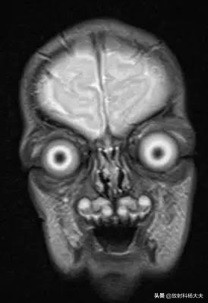

比如,一个猝不及防就收到来自患者冠状位的凝视。。。

(请大家做好心理准备,我要给大家上两张我的珍藏)

这一张我一直觉得可以过年贴门上辟邪

这张我考虑联系一个致力于拍鬼片的独立导演,卖给他做封面宣传

注:以上图像和颜值没有任何关系,相信我,无论是女神、小鲜肉、还是国民级老公,都经不起头颅核磁冠状位的考验